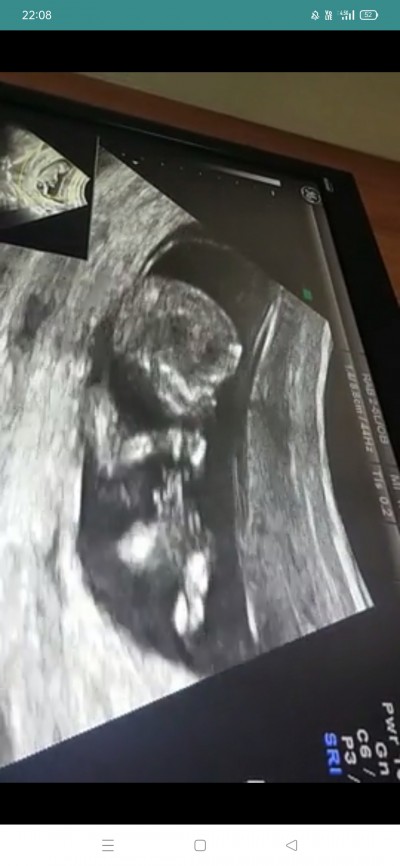

17 Eylül 2021 Hamilelik Dönemi Genel kategorisinde (94 puan) sordu

Öğrenmek nasip olmadı bir türlü :(

Gebelik haftası 19+1

Çünkü bacaklarını kapatmış miniş :) sabırlı olun kızımda bizde çok geç öğrendik göstermedi

Bence erkek bu kizlar daha ince oluyo ilk zamanlar sanki benim fikrim :)

Sizi çok iyi anlıyorum doktorumla yarim saat bakardık bacaklarını açsın uygun bir pozisyona gelsin diye. Ayrıntılı ultrasonda öğrendik 22. Haftada. İnsan gerçekten merak ediyor ama çok yakında öğrenirsiniz.